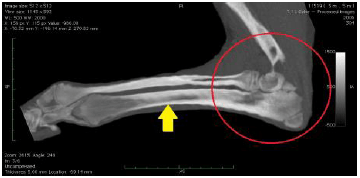

1. ボルゾイの前足の骨折(橈尺骨骨折)

ボルゾイという大型犬の前足を横から見たレントゲン写真です。 前足の骨が折れて曲がっています。(白矢印) 骨にヒビが入っている部分もあります。(黄色矢印) |